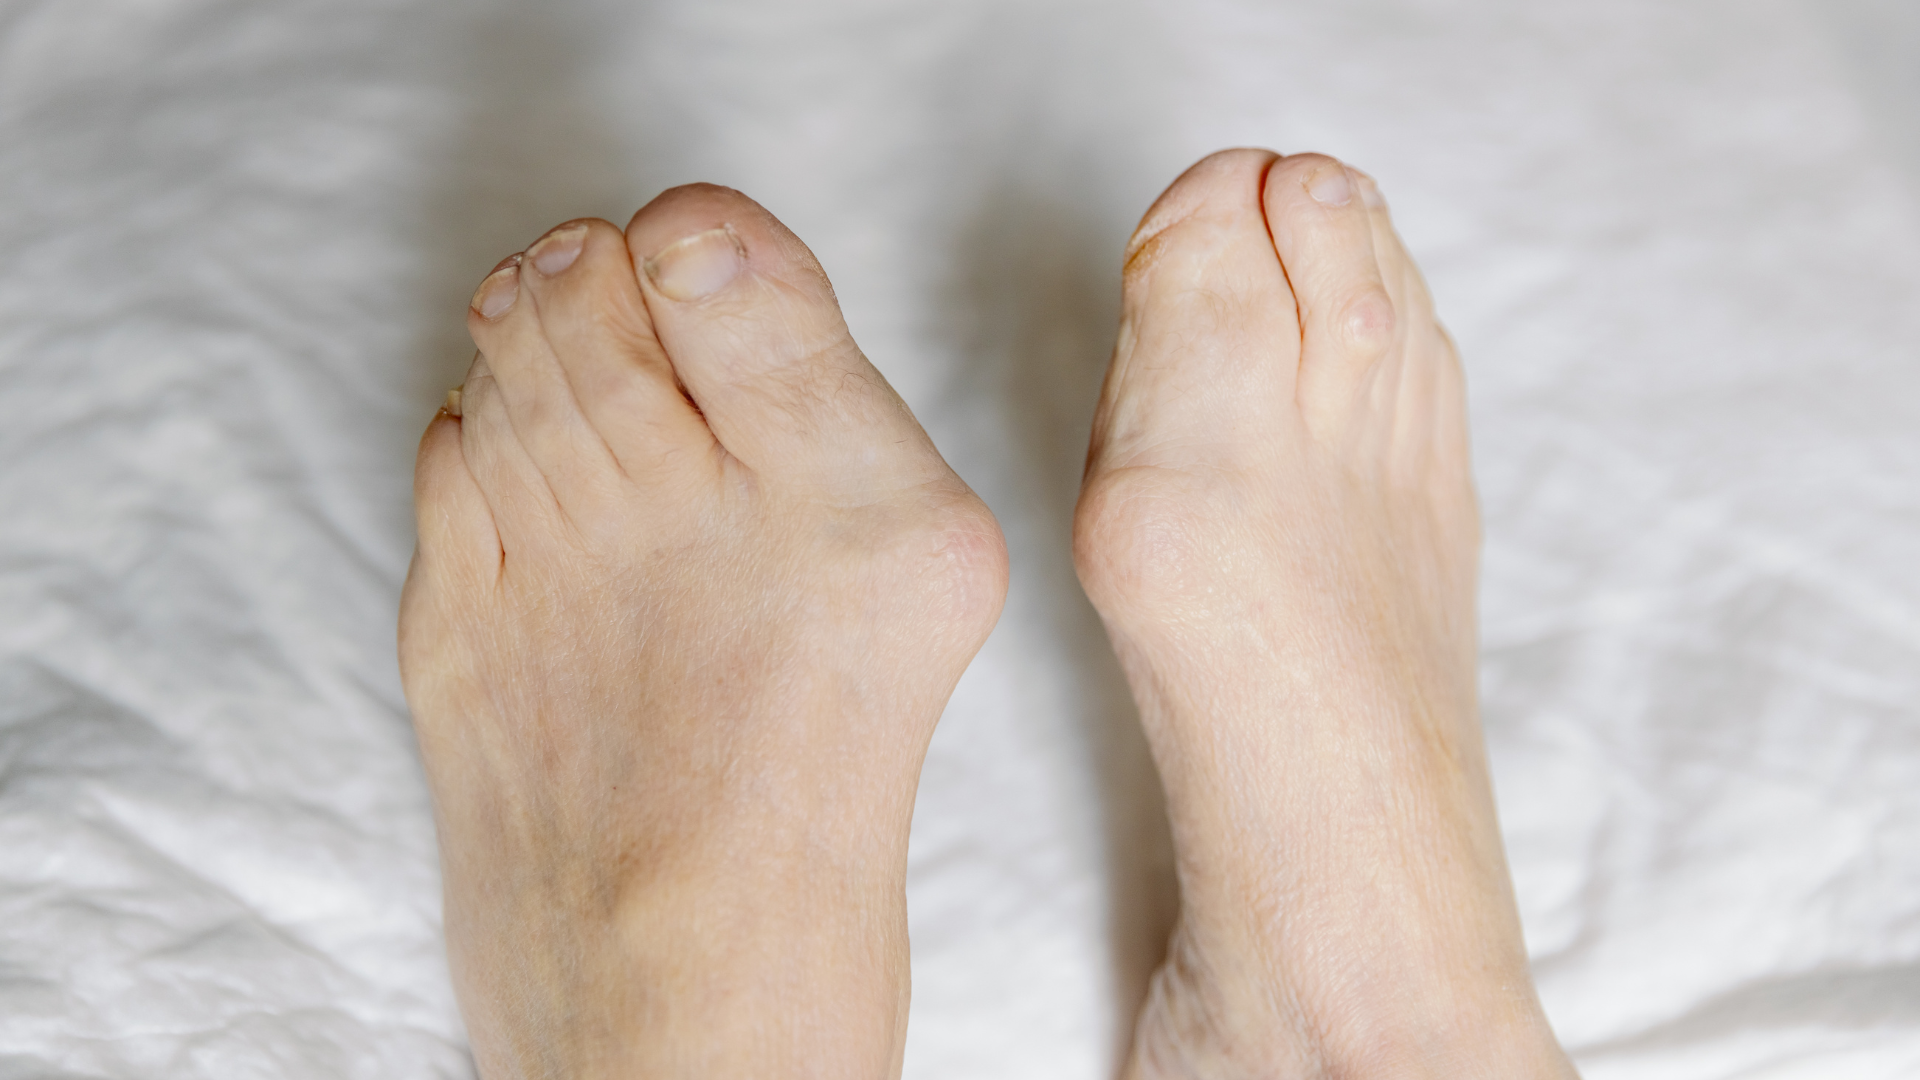

- Biến dạng khớp, mất cấu trúc bình thường của khớp.

- Hạn chế vận động hoặc mất khả năng vận động, ảnh hưởng đến sinh hoạt hằng ngày.

- Có dấu hiệu biến dạng khớp hoặc yếu cơ quanh khớp.